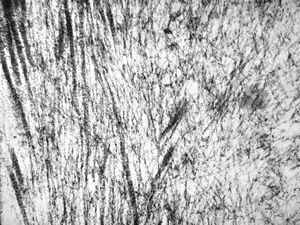

F,39y. | collagen and elastin - aorta

F,39y. | collagen, elastin and oxytalan microfibrils

F,45y. | collagen fibril - skin

F,29y. | collagen, elastin and oxytalan microfibrils - endomyocardial fibrosis